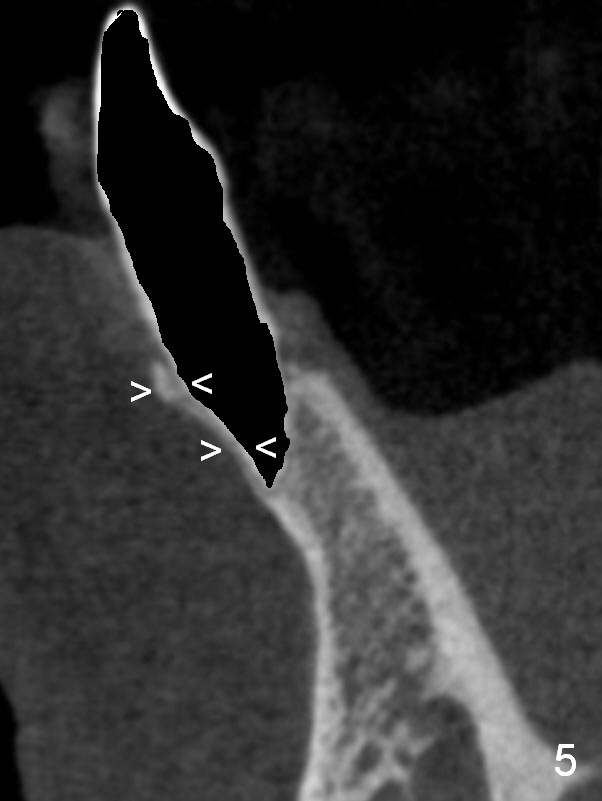

A 74-year-old man has several missing teeth (Fig.1).  His 1st goal is to replace the lower left lateral incisor (Fig.2).  The residual root has an apical lesion (Fig.3 *).  To describe intraop findings, a CT image of a different patient is used (Fig.4 coronal section; B: buccal; L: lingual).  After extraction, the buccal plate is found to be thin and low (Fig.5 arrowheads).  A 1.5 mm pilot drill (Fig.6 red line) is used to initiate osteotomy in the lingual plate of the socket.  Once the drill penetrates the lingual plate, the trajectory changes and the depth is 17 mm from the gingival margin (Fig.7).  A PA is taken (Fig.8); it appears that the osteotomy can be extended more apically.  When the pilot drill extends to 20 mm, there is sudden empty feeling.  The lingual plate has perforated (Fig.9).  A new osteotomy is established buccally (Fig.10 pink).  To avoid buccal plate perforation, especially in the buccal undercut area (>), the coronal end of the drill has to be tilted buccally (<--).  An angled abutment (3x20 mm, 15°) is placed (Fig.11,12).  The abutment is modified (Fig.13,14) to accommodate an immediate provisional (Fig.15,16 P).  Perio dressing is to be applied to prevent the bone graft from getting dislodged buccally (Fig.15).  The dressing is in place 7 days postop (Fig.17).